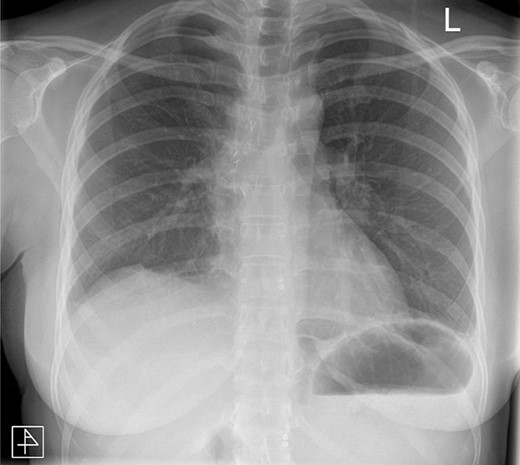

The post-operative course was unremarkable. The chest drain was removed on Day 2, and the patient was discharged on Day 3. The patient has since been reviewed in clinic and is well. Follow-up radiographs demonstrated absence of any remaining pathology (Fig. 5).